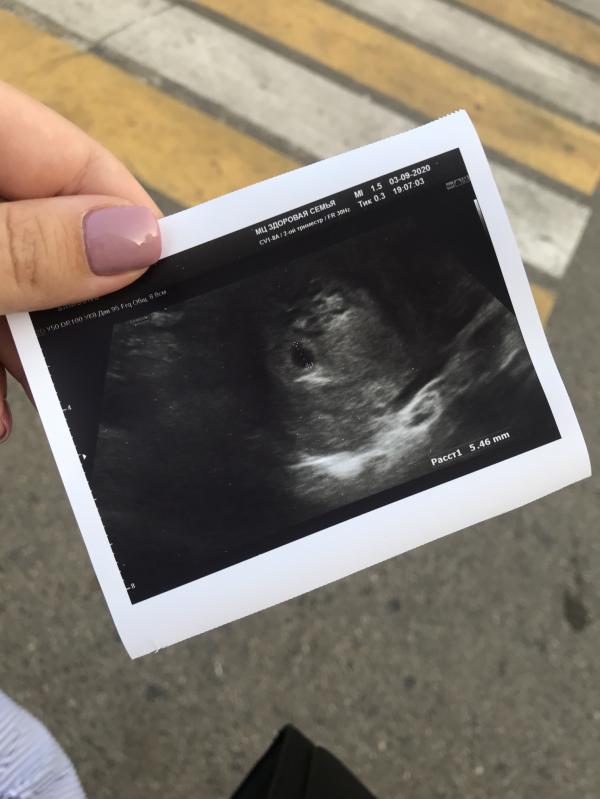

4 недели и 5 дней беременности по акушерскому сроку

Плодное яйцо 5,4мм, желтое тело 24мм (да, в левом яичнике, где я и чувствовала овуляцию)